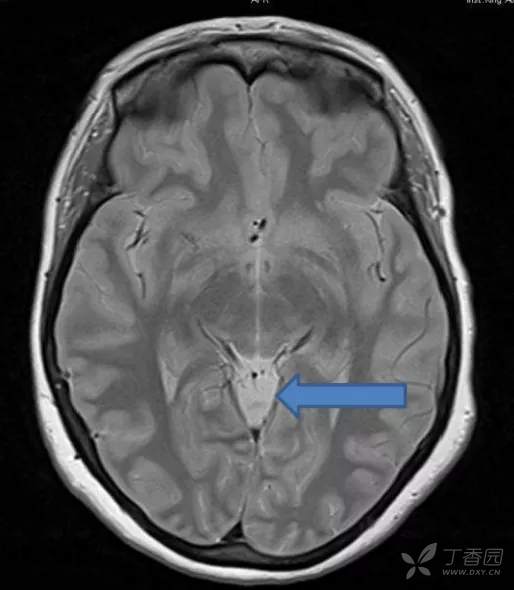

帆间池

帆间池 cistern of velum interpositum, 又称中间帆腔或第三脑室上池,位于第三脑室顶的上方、穹隆体和穹隆连合的下方。

它是一尖向前的三角区,两前外侧界为穹隆的内侧缘,后界为胼胝体压部。

此腔可经胼胝体压部的下方通大脑大静脉池。

在临床工作中,应注意帆间池与第三脑室顶部的区别:

1、帆间池的层面较高,第三脑室顶部层面较低;

2、帆间池后界是胼胝体压部,第三脑室顶部的后界为松果体;

3、帆间池为尖向前的三角区,不与侧脑室前角相连;而第三脑室前部为矢状位的狭长裂隙,前端可达侧脑室前角。